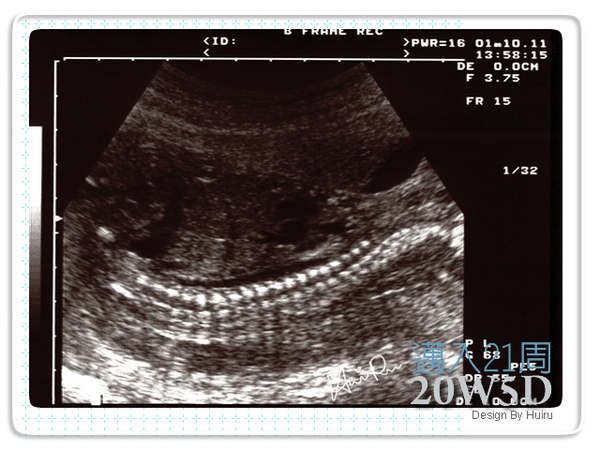

很清楚地脊椎咧~